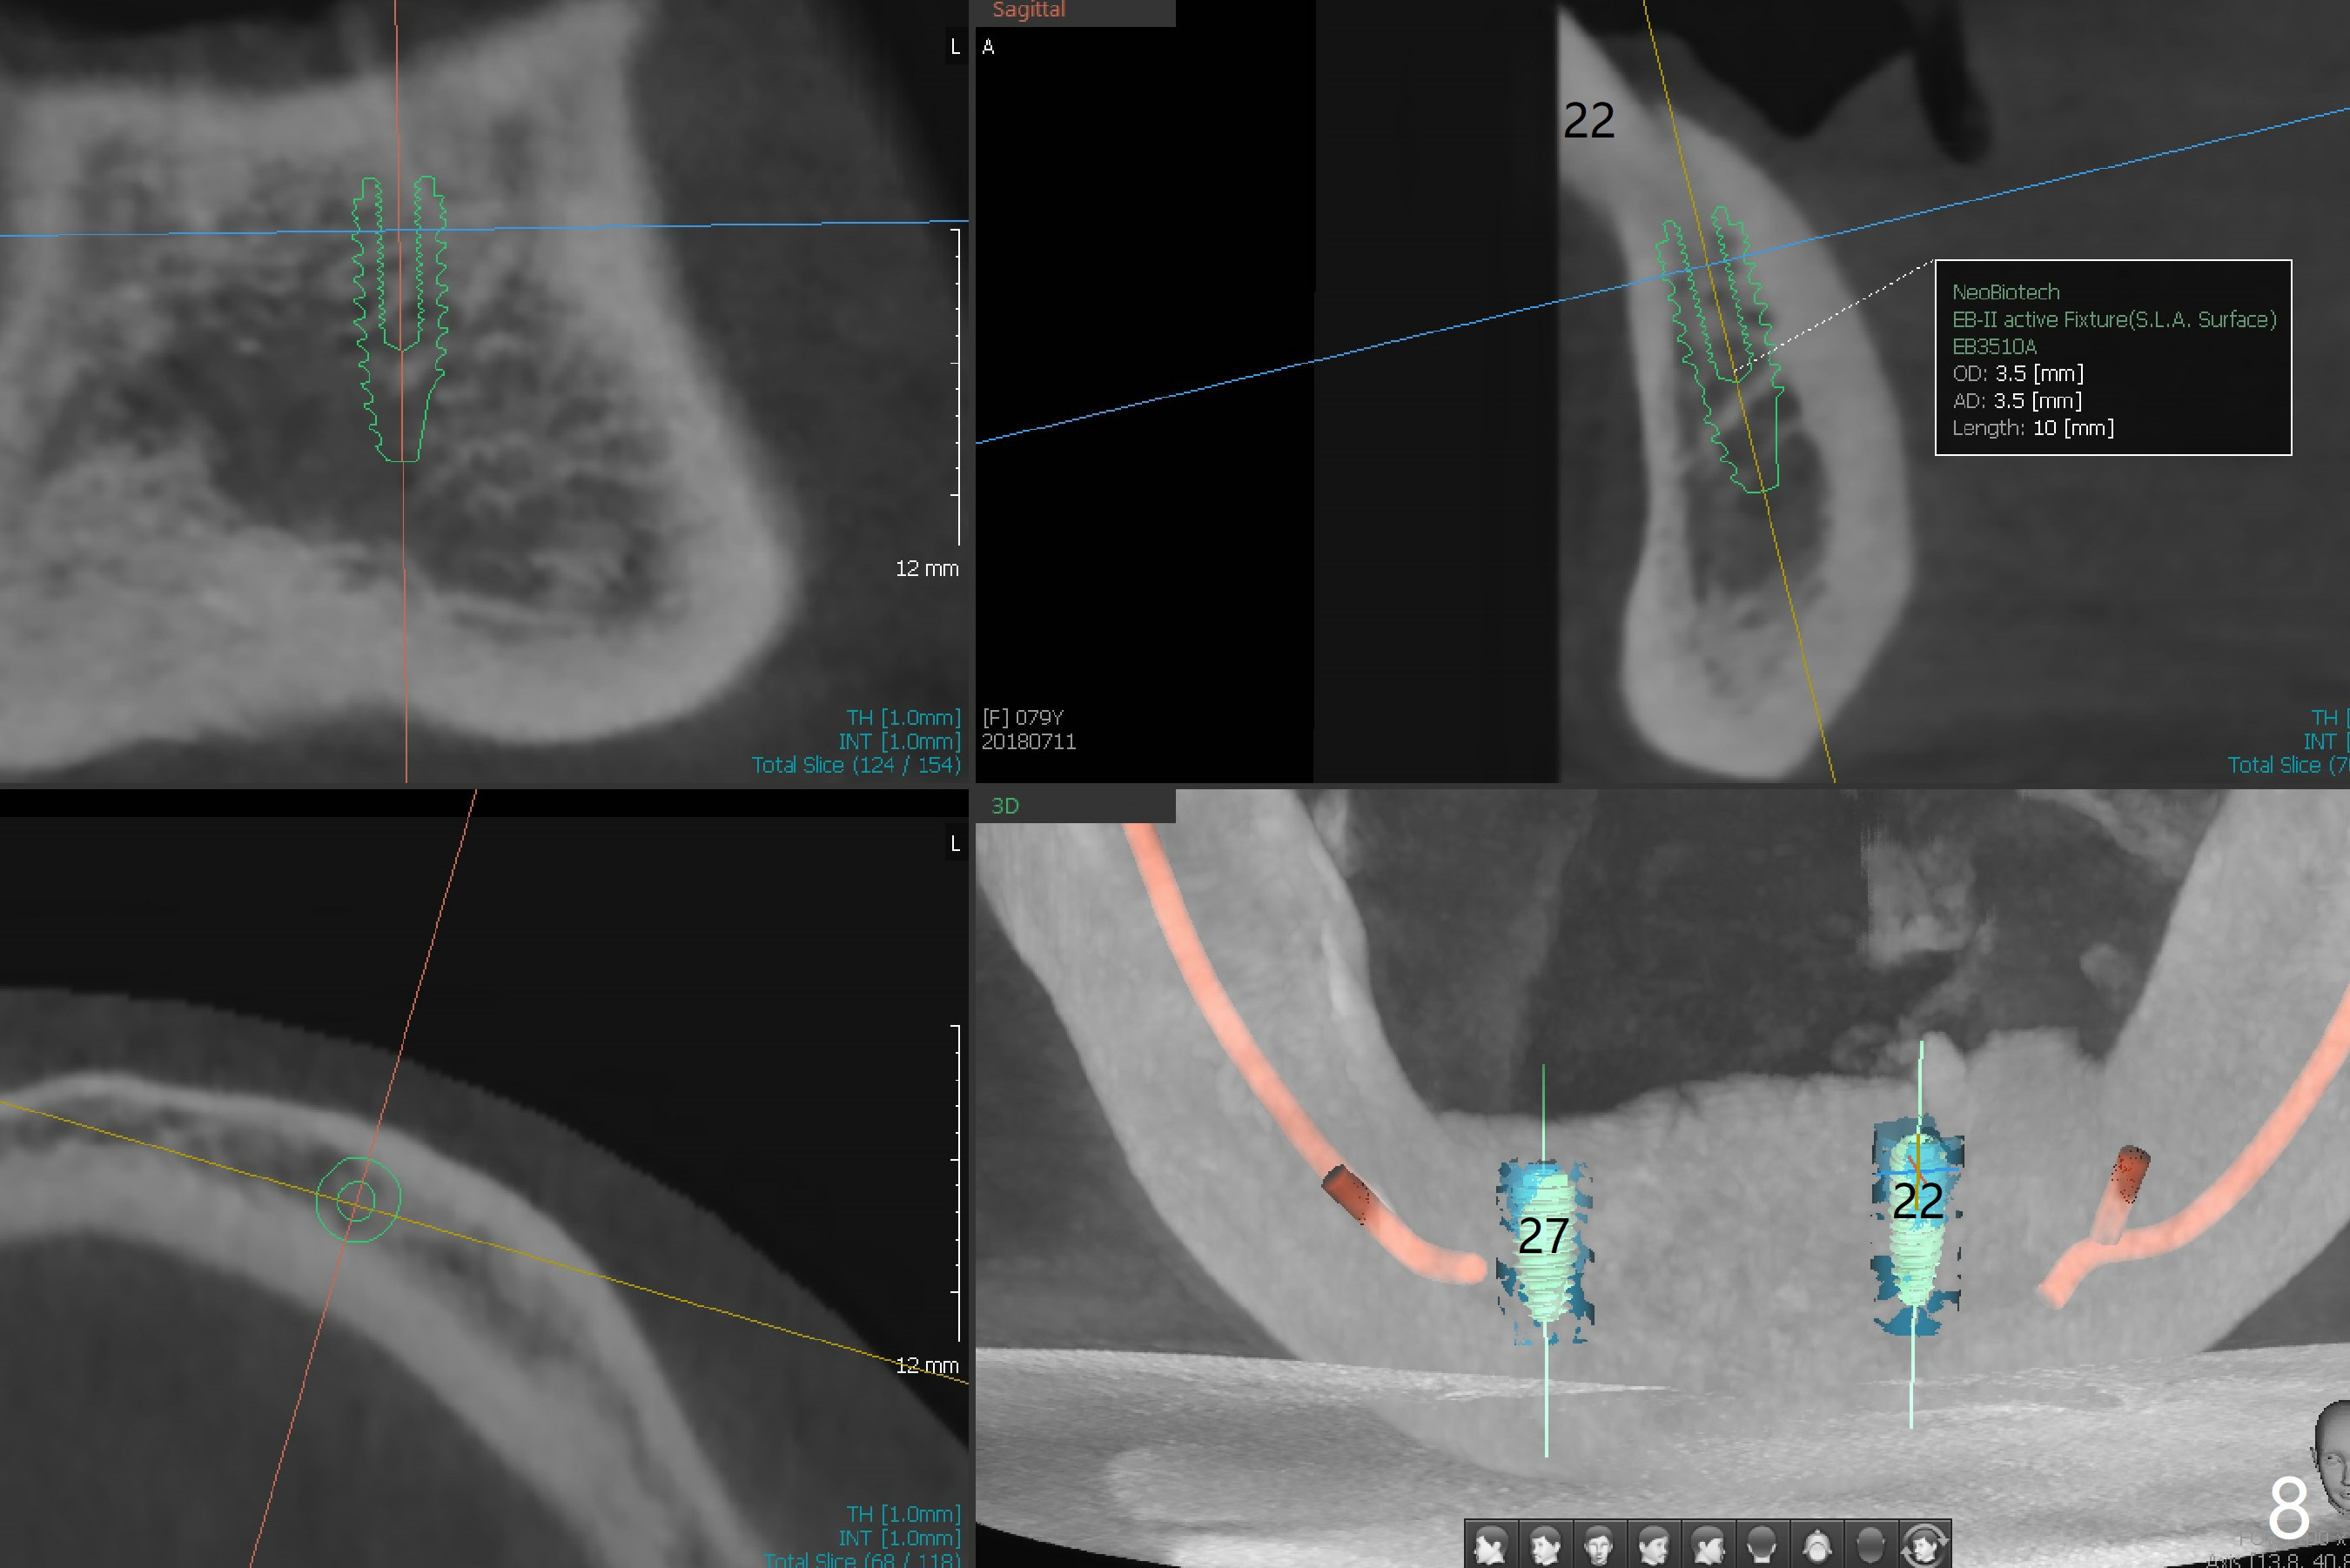

A 79-year-old woman is not pleased with cross bite and no tooth exposure of the upper complete denture (Fig.1-4). Her immediate concern is the loose lower RPD (Fig.5) after loss of the tooth #21 (Fig.6). The tooth #22 has mobility II. SM narrow implants will be placed at #22 and 27 immediately after #27 extraction (Fig.7,8). Ball abutments are going to be inserted prior to soft reline of the lower RPD. Prepare an acrylic bur to make a receptacle in the RPD for #27 abutment and high speed handpiece to section the tooth #22 as a denture tooth (prepare hard pink acrylic)